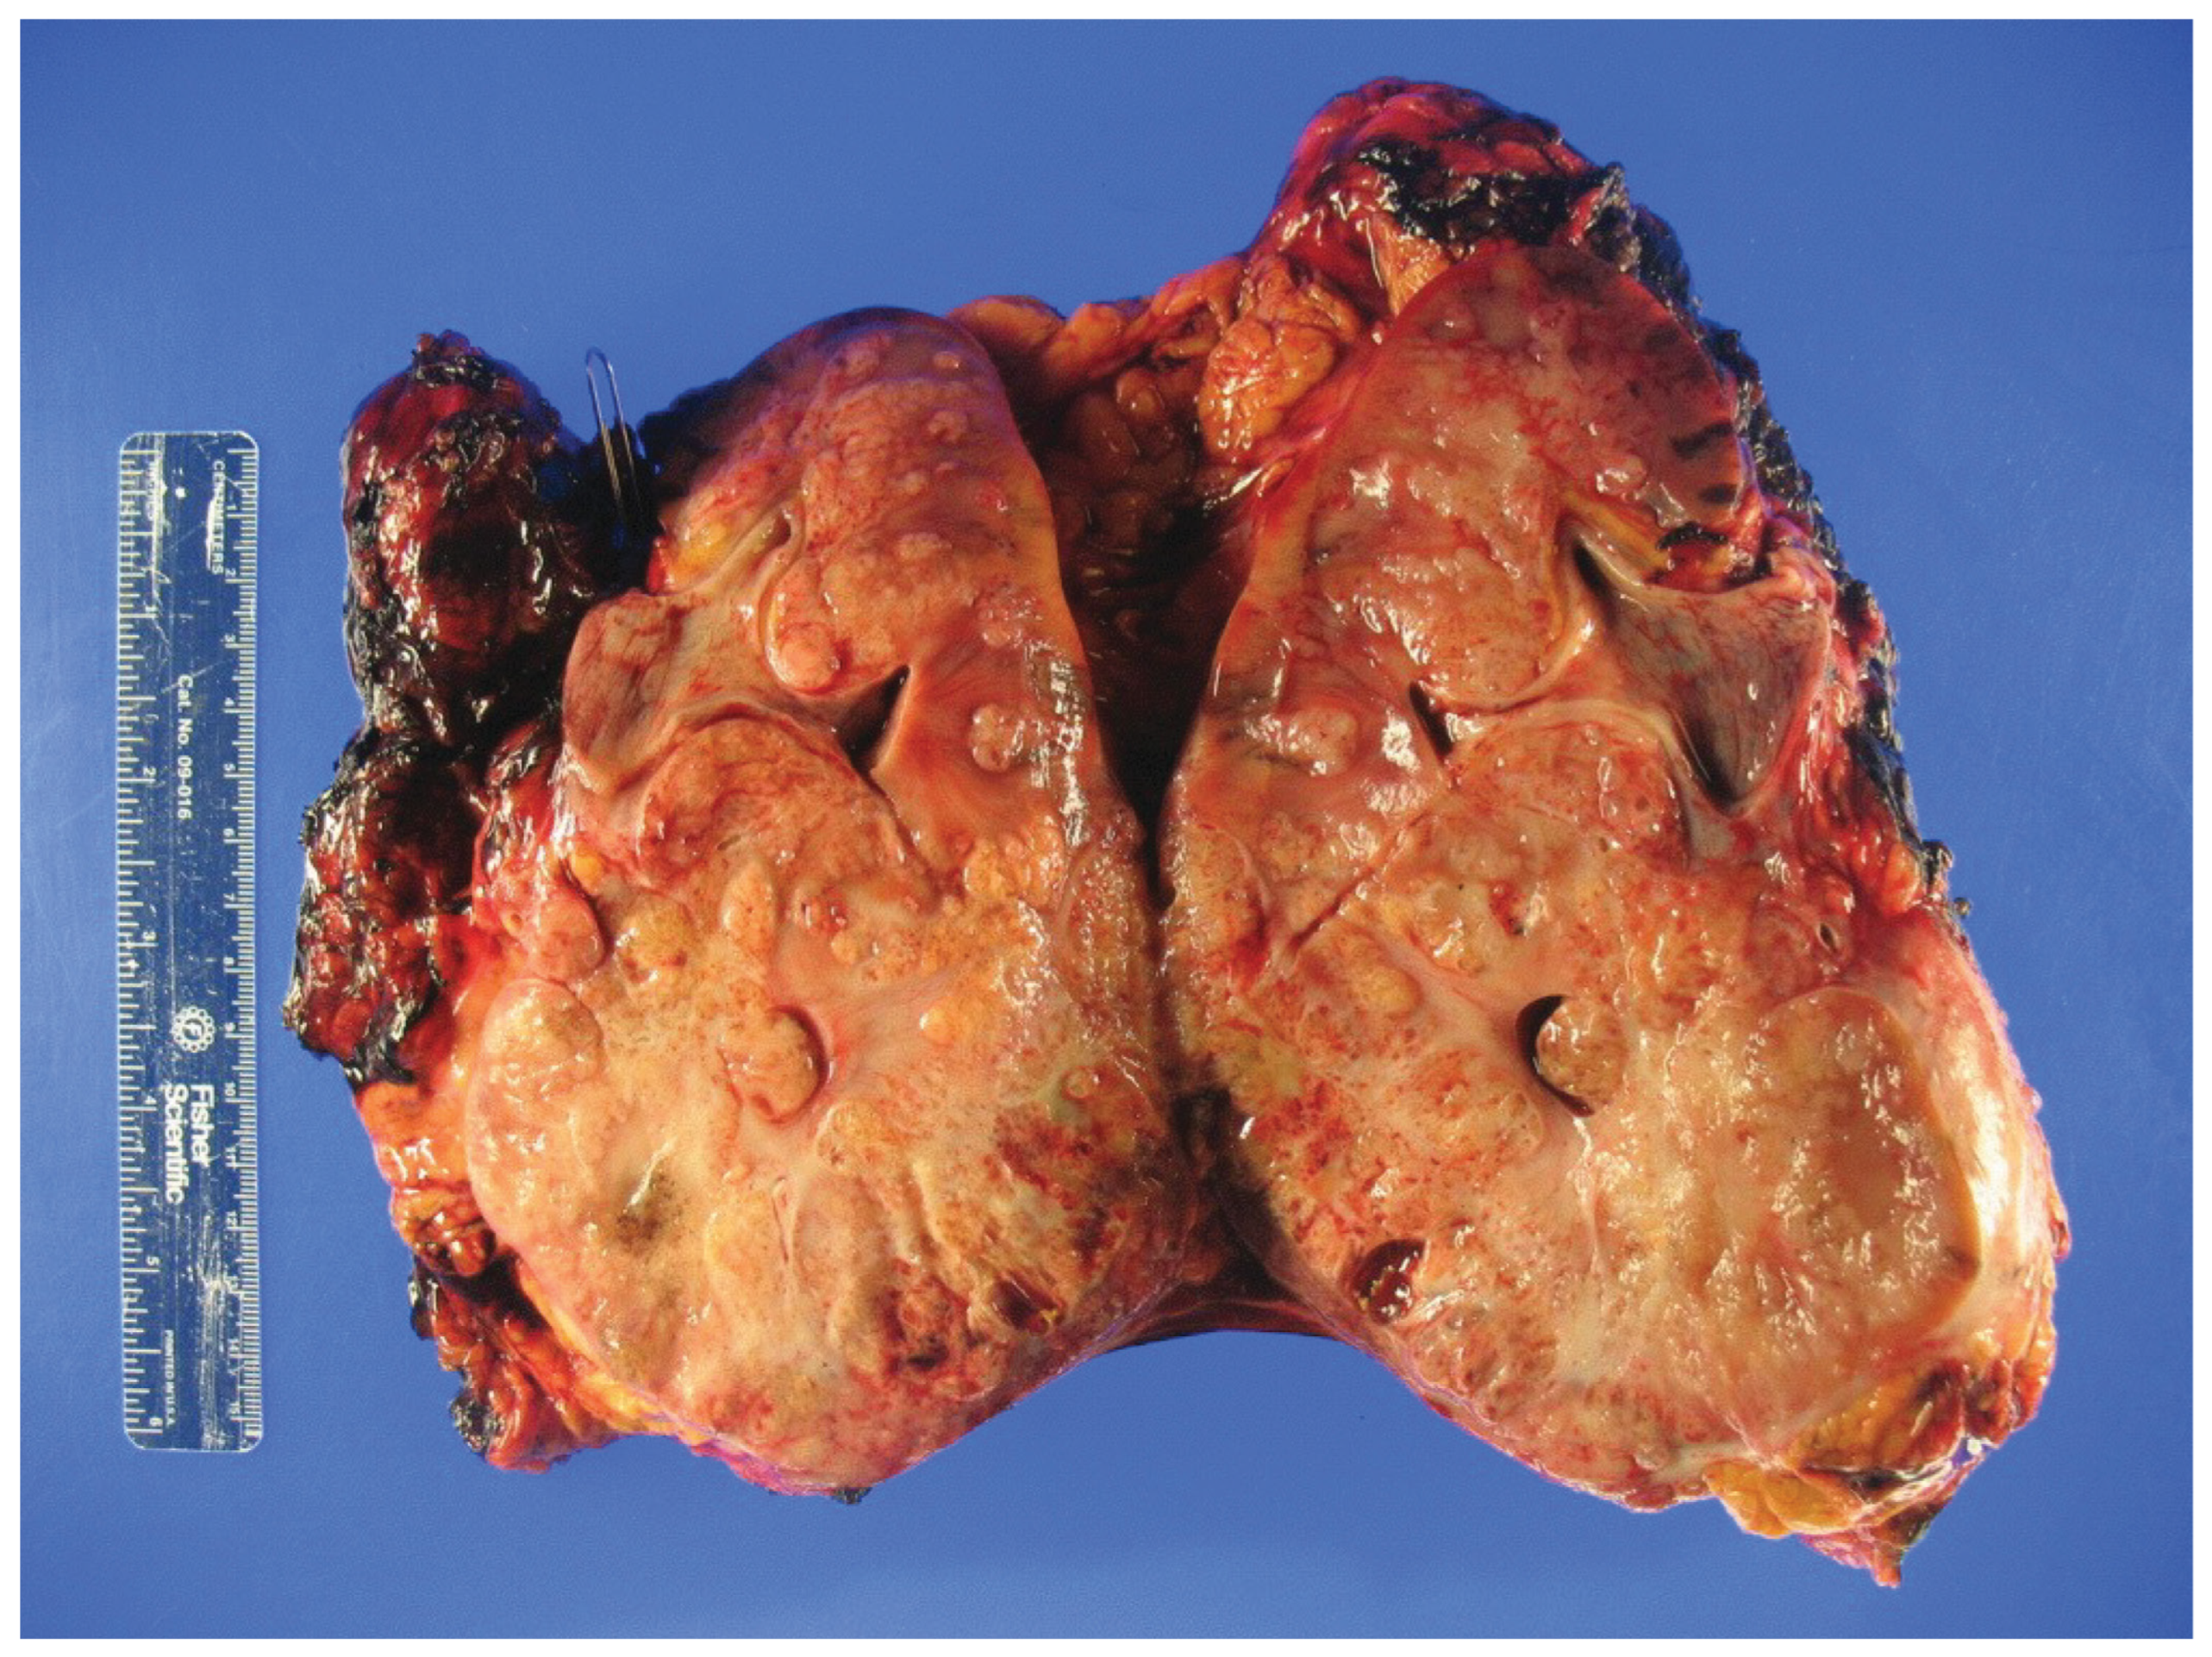

Figure 1.

Gross inspection of a radical nephrectomy specimen showing hereditary leiomyomatosis and renal cell carcinoma (HLRCC) with an infiltrative tumor appearance.

HLRCC was first described 50 years ago as the autosomal dominant familial Reed’s syndrome of cutaneous leiomyomas [27]. Recognition of associated uterine leiomyomas and RCC led to the designation of HLRCC [28]. In 2002, fumarate hydratase (FH) was identified as the causal TSG [ 29]. HLRCC was initially thought to be a rare disease with high penetrance, but recent data suggests that HLRCC may have an incidence as high as 1 in 1000 [30] with highly variable penetrance [31,32]. Cutaneous leiomyomas are observed in 50% to 80% as raised skin papules that may be painful. Uterine leiomyomas are reported in 30% to 80%. Though benign, they can present with heavy vaginal bleeding and early hysterectomy. FH-deficient RCC occurs in 10% to 20% and is notoriously aggressive, with early progression to metastatic disease [31,32,33]. Median age of onset is 36 to 40 years (range, 11–90 years) [17,34] and 7% present under the age of 20. If not detected by screening, RCC presents with symptoms from advanced disease (Figure 1) [33,35]. To date, most RCCs have been unifocal. However, with screening and effective early treatment, metachronous tumors have now been reported. FH-deficient RCC histology is variable and includes type 2 papillary, collecting duct, or tubulocystic morphology [32,35], frequently with two or more growth patterns, and pleiomorphic eosinophilic nucleoli surrounded by a clear halo [32].